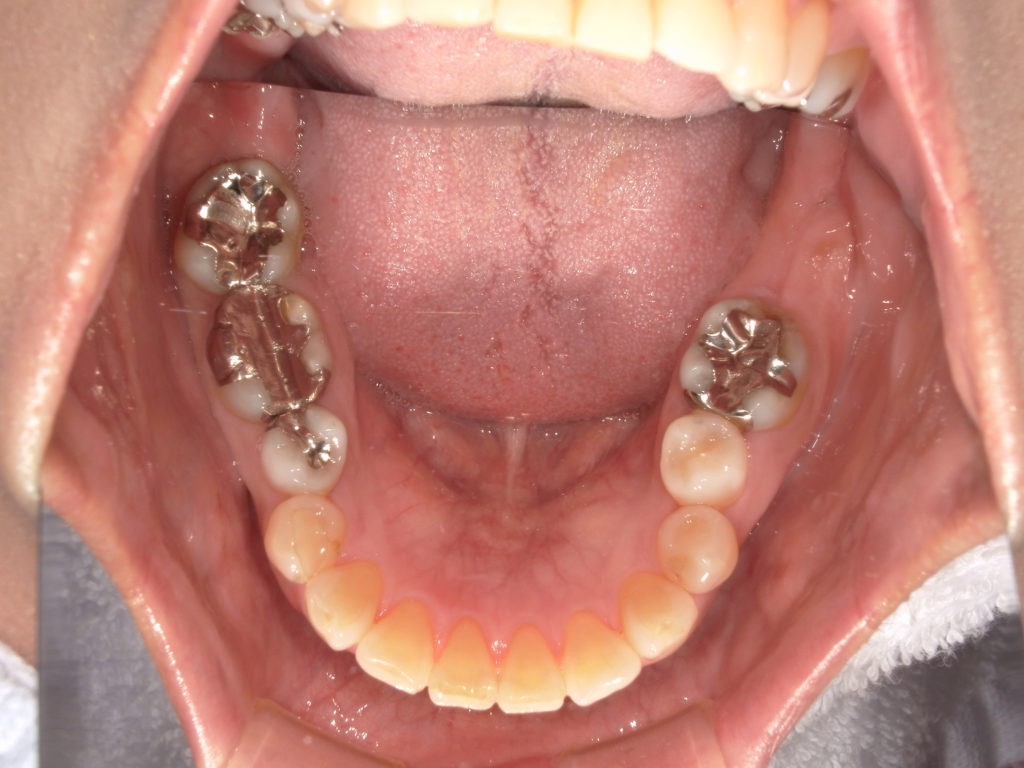

Y様インプラント実例 #44

左の上下の奥歯をインプラントで治療しています。

左下の奥歯は歯を抜くのと同時にインプラントの埋め込みを行っています。

被せものは上下、セラミックスで作っています。

治療前

治療後